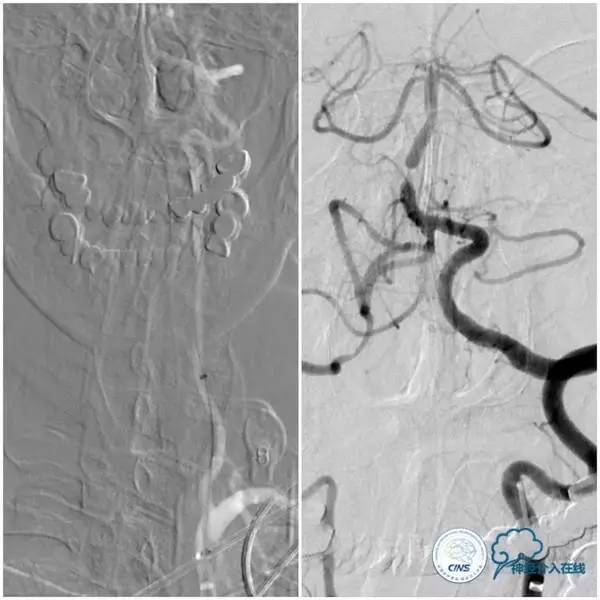

全麻下右侧股动脉穿刺置入6F动脉鞘,交换置入7F长鞘(70cm)置于左锁骨下动脉近端,沿长鞘送入6F Navien导管(115cm)置于左椎动脉V2段以远,造影示基底动脉近段重度狭窄(图7)。

图7

Pilot微导丝(0.014”,190cm)路径图下小心通过基底动脉近端狭窄段至左小脑前下动脉,沿微导丝送入Ultra-soft (2.0×20mm)球囊至基底动脉近端狭窄段预扩张(图8)。

图8